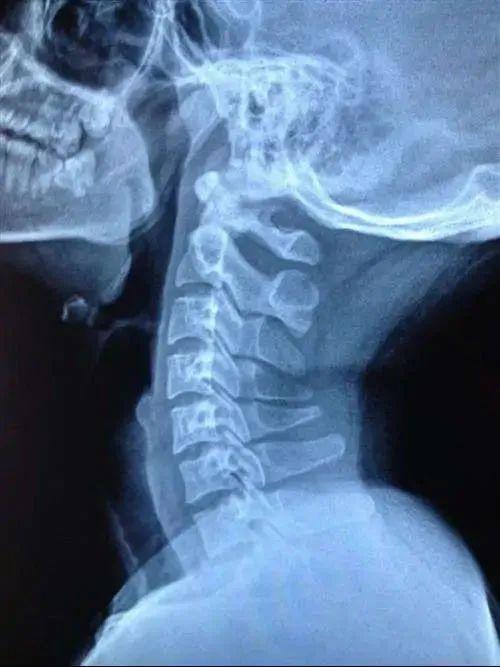

儿童颈椎骨突出图片

儿童颈椎x光片

儿童颈椎影像

儿童颈椎x线